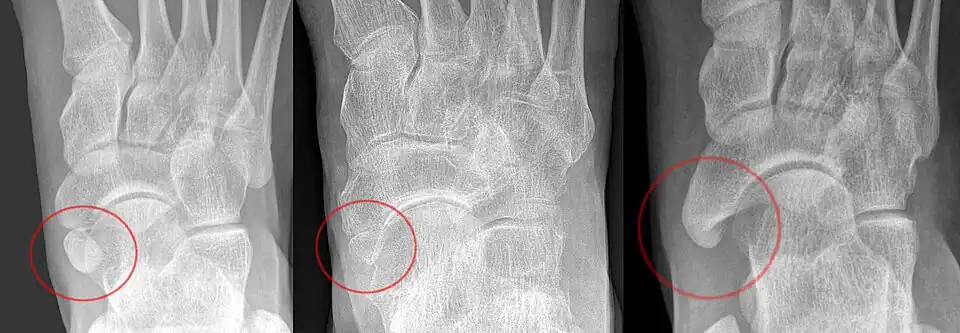

Accessory navicular

An accessory navicular bone, also called os tibiale externum, occasionally develops in front of the ankle towards the inside of the foot. This bone may be present in approximately 2–21% of the general population and is usually asymptomatic.[18][19][20] When it is symptomatic, surgery may be necessary.

The Geist classification divides the accessory navicular bones into three types.[20]

- Type 1: An os tibiale externum is a 2–3 mm sesamoid bone in the distal posterior tibialis tendon. Usually asymptomatic.

- Type 2: Triangular or heart-shaped ossicle measuring up to 12 mm, which represents a secondary ossification center connected to the navicular tuberosity by a 1–2 mm layer of fibrocartilage or hyaline cartilage. Portions of the posterior tibialis tendon sometimes insert onto the accessory ossicle, which can cause dysfunction, and therefore, symptoms.

- Type 3: A cornuate navicular bone represents an enlarged navicular tuberosity, which may represent a fused Type 2 accessory bone. Occasionally symptomatic due to bunion formation.

Os trigonum

The os trigonum or accessory talus represents a failure of fusion of the lateral tubercle of the posterior process of the talus bone. Is estimated to be present in 7–25% of adults.[17] It can be mistaken for an avulsion fracture of lateral tubercle of talus (Shepherd fracture) or a fracture of the Stieda process. In most cases, Os Trigonum will go unnoticed, but with some ankle injuries it can get trapped between the heel and ankle bones which irritates the surrounding structures, leading to Os Trigonum Syndrome.[21]